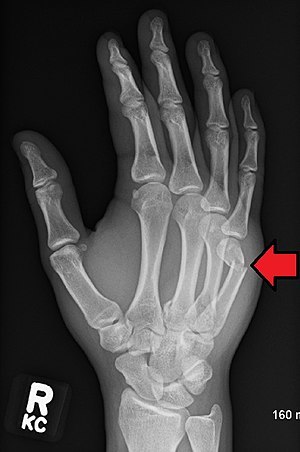

What bone is typically located in ‘boxer #’? (punching a hard surface)

5th metacarpal neck